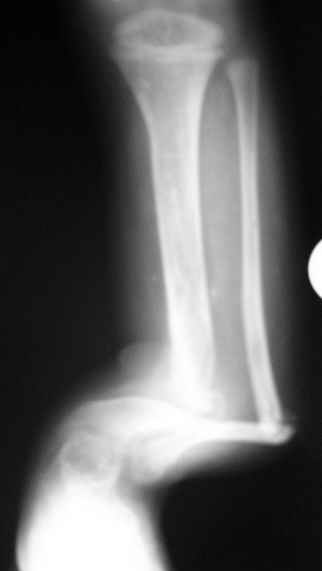

Уважаемые коллеги,Госпитализировали ребенка 4 лет с врожденной деформацией голени.

Редко встречающаяся патология , но за последние два года у нас наблюдается

уже третий ребенок, в одном случае деформация сочеталась с

нейрофиброматозом.

Все деформации были односторонними на уровне нижней трети голени и

диспластического типа с полной окклюзией к.м. канала.